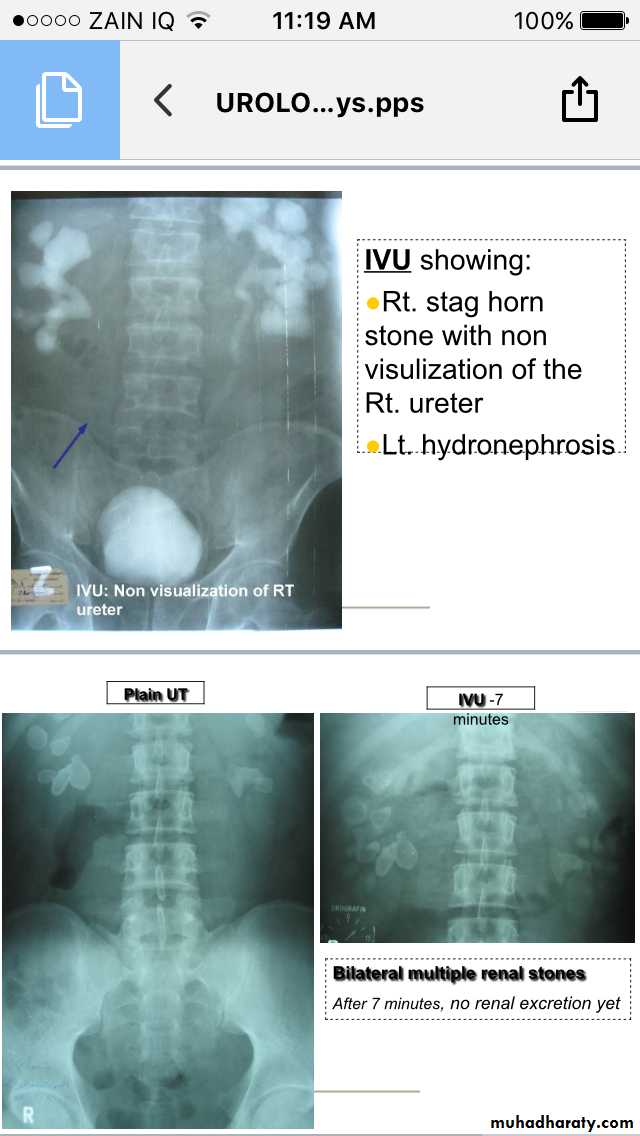

IVU

Renal stones

Ureteric stones